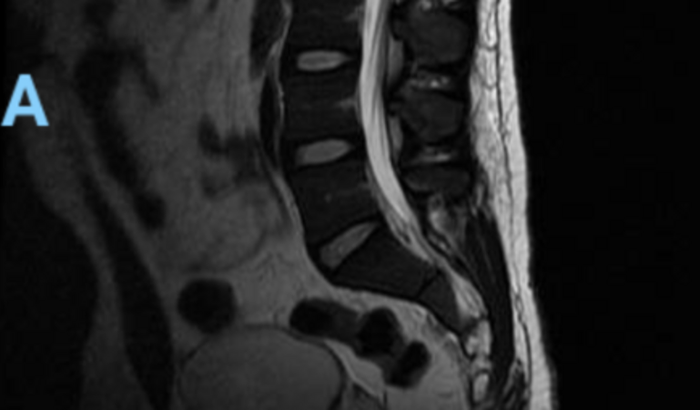

Meu marido desenvolveu uma condição rara de abscesso, num músculo chamado Psoas. Isso é, contraiu uma infecção causada por bactéria, gerando uma inflamação, que fez com que, além desse problema por si só, causasse uma dor inimaginável, pois o nervo ciático foi comprimido. Todo esse quadro o deixou impossibilitado, literalmente de cama, com dificuldades de levantar, sentar, andar ou realizar qualquer momento. Acabou perdendo os movimentos da perna esquerda. Ficou impossibilitado também de trabalhar.

Foram muitas consultas, algumas visitas a emergência por causa da dor e também um exame de ressonância magnética até que o problema pudesse ser identificado, mas estava só começando a história.